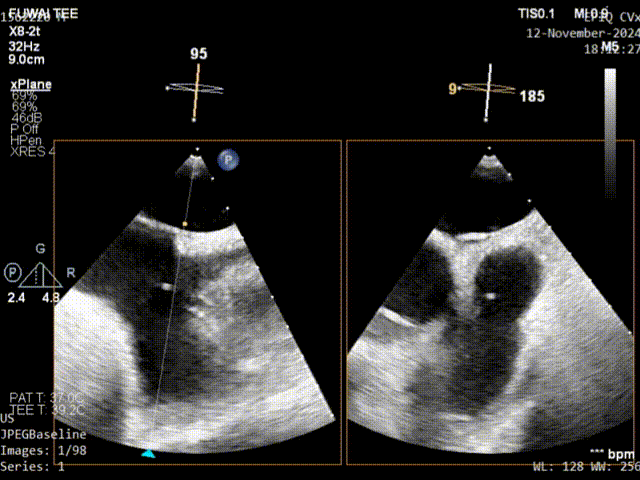

术前TEE影像